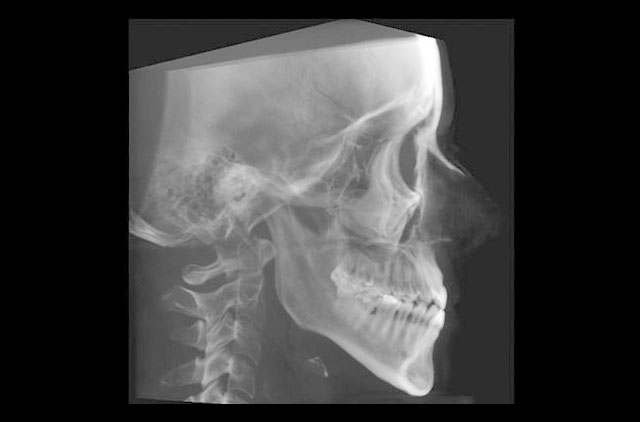

-Lateral de Cráneo 8x10" (LC)

-Lateral de Cráneo 10x12" (LC)

-Anteroposterior (AP)

-Posteroanterior (PA)